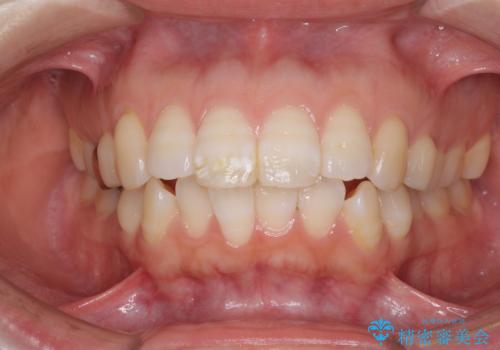

- 口元の閉じにくさと、前歯のでこぼこの歯並びを気にして来院された患者様です。

口元を積極的に引っ込めるために、上下左右の小臼歯計4本を抜歯することとしました。

セオリーでは第一小臼歯を抜歯しますが、上下右側は第二小臼歯に銀歯が装着されているため、第二小臼歯を抜歯することとしました。

上下正中を左右対称に揃えるため、アンカースクリューや補助装置を使用しながら口元を下げていくこととしました。

積極的に前歯を牽引したことで、口元の閉じにくさは顕著に改善され、横顔のシルエットが大幅に変化しました。